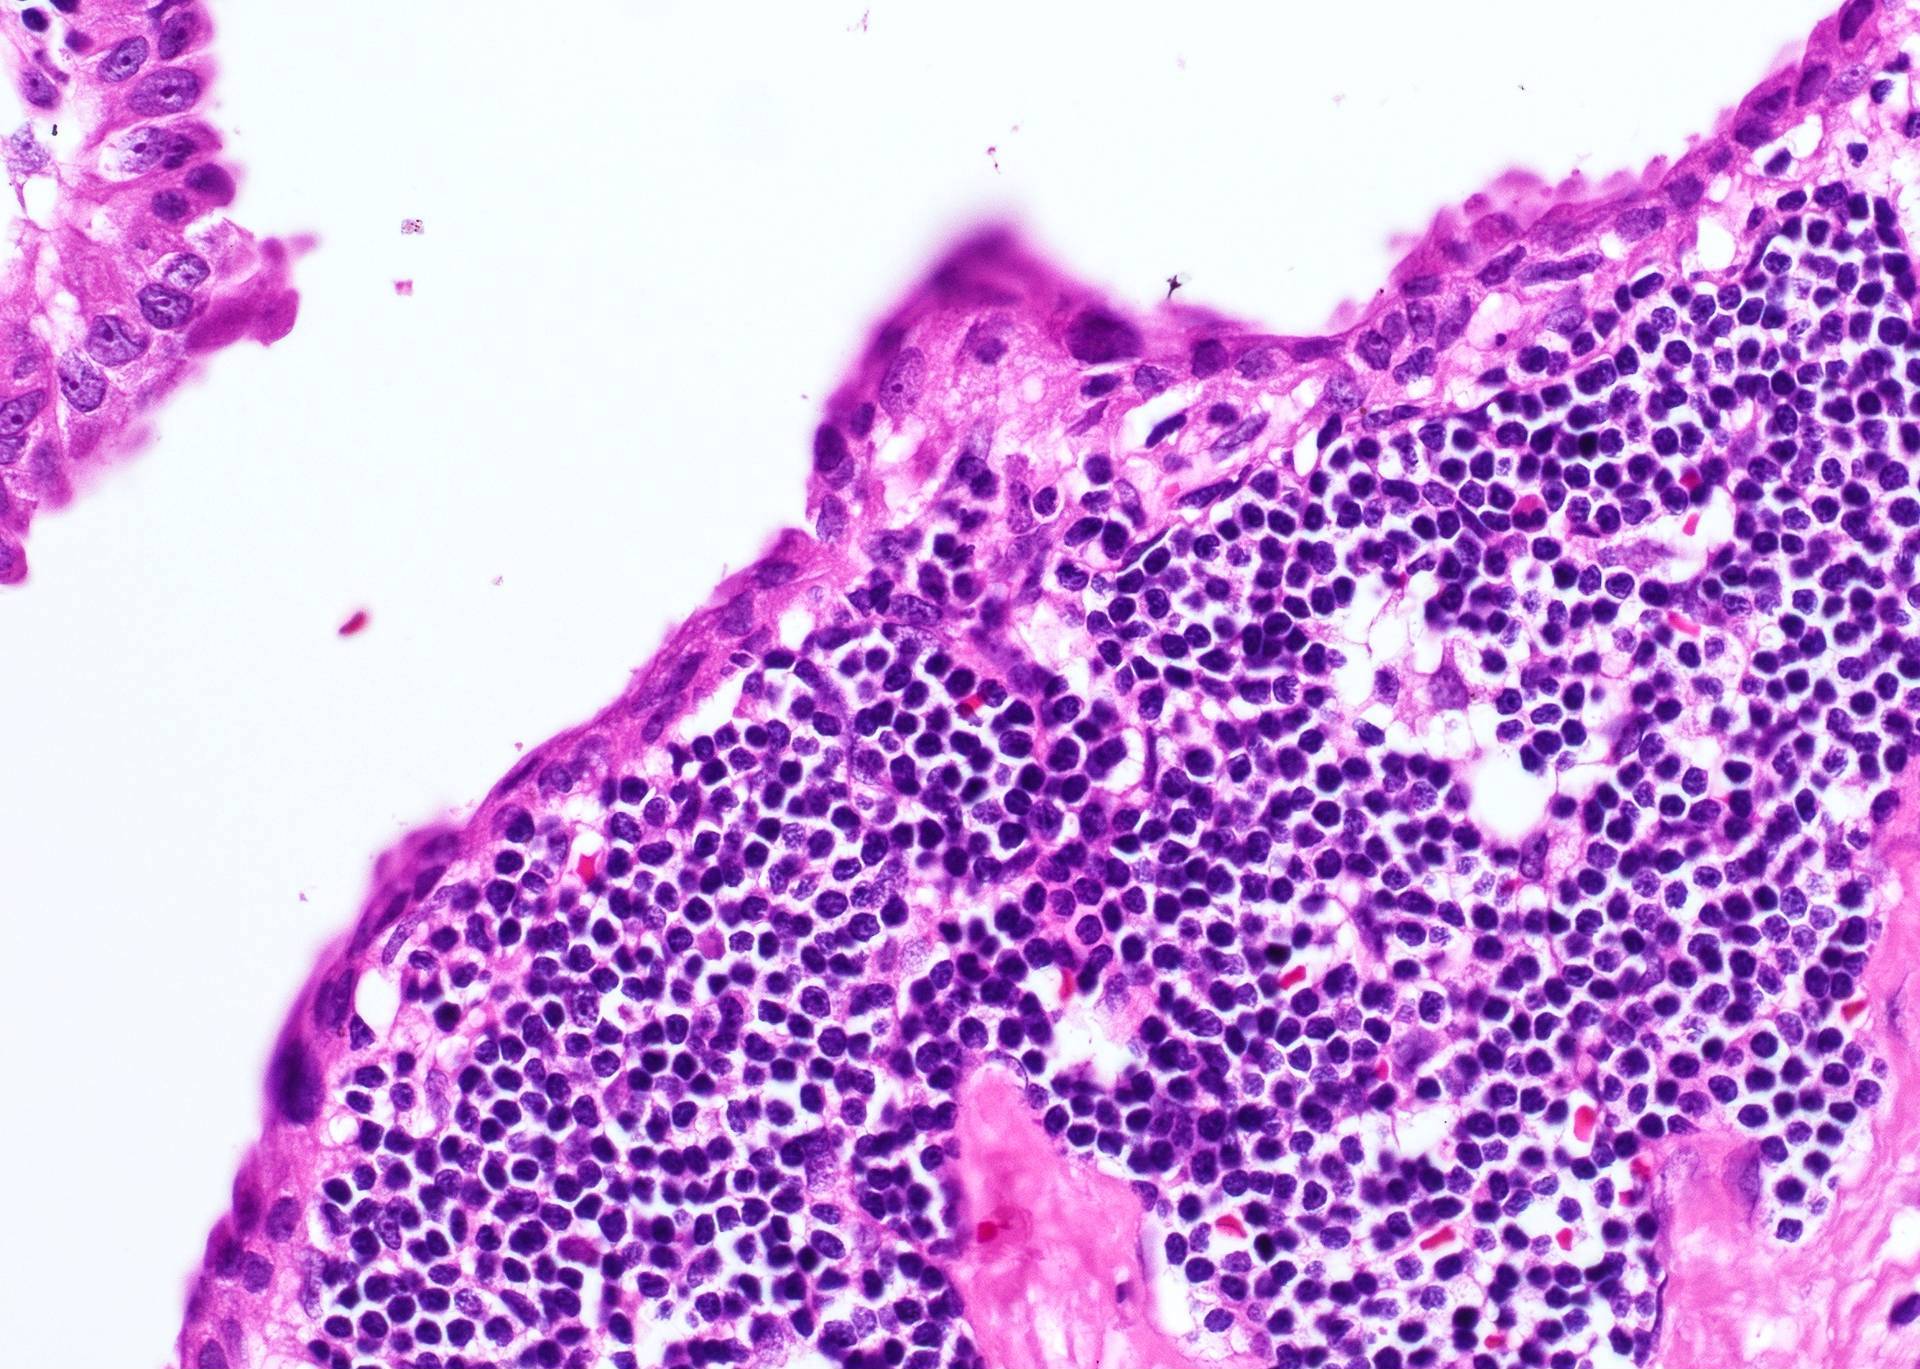

- Stratified squamous or ciliated columnar epithelium lining (Am J Pathol 1967;50:765, APMIS 1997;105:623)

- Fibrotic wall with lymphoid follicles resembling lymph node or tonsil

- May be secondarily infected

- Cysts may have sebaceous or mucinous glands